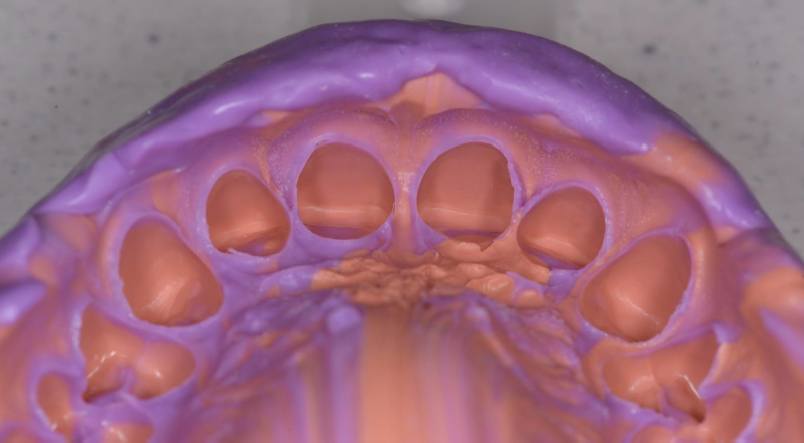

A teeth model, an impression of the patients teeth

One-step impression taken with 3M™ Express™ XT Penta H and 3M™ Express™ XT Light Body impression materials.